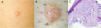

Varón de 62 años que consultó por una lesión en muslo derecho de dos años de evolución. La exploración objetivó un nódulo firme, de superficie brillante (figura 1A). A la dermatoscopia se presentaba como una lesión de bordes festoneados, translúcida, de coloración rosa-blanquecina, con una pequeña costra central. Asimismo, se visualizaron vasos finos en superficie y manchas blancas homogéneas en el interior (fig. 1B).

El estudio anatomopatológico tras la exéresis quirúrgica de la lesión puso de manifiesto una proliferación mesenquimal mixoide muy hipocelular, que contenía células estrelladas sin atipia y frecuentes estructuras vasculares, lo que fue compatible con angiomixoma superficial (fig. 1C).El angiomixoma superficial es un tumor mesenquimal benigno e infrecuente, que afecta predominantemente tronco y extremidades de varones de edad media y puede asociarse con el complejo de Carney. Su dermatoscopia ha sido escasamente publicada. Se ha descrito el «signo del planeta rojo» como patrón dermatoscópico característico, que corresponde a glóbulos translúcidos rojizos con vascularización fina superficial. La diferencia de coloración respecto a nuestro caso probablemente se deba a la heterogeneidad clínica con la que se manifiesta.